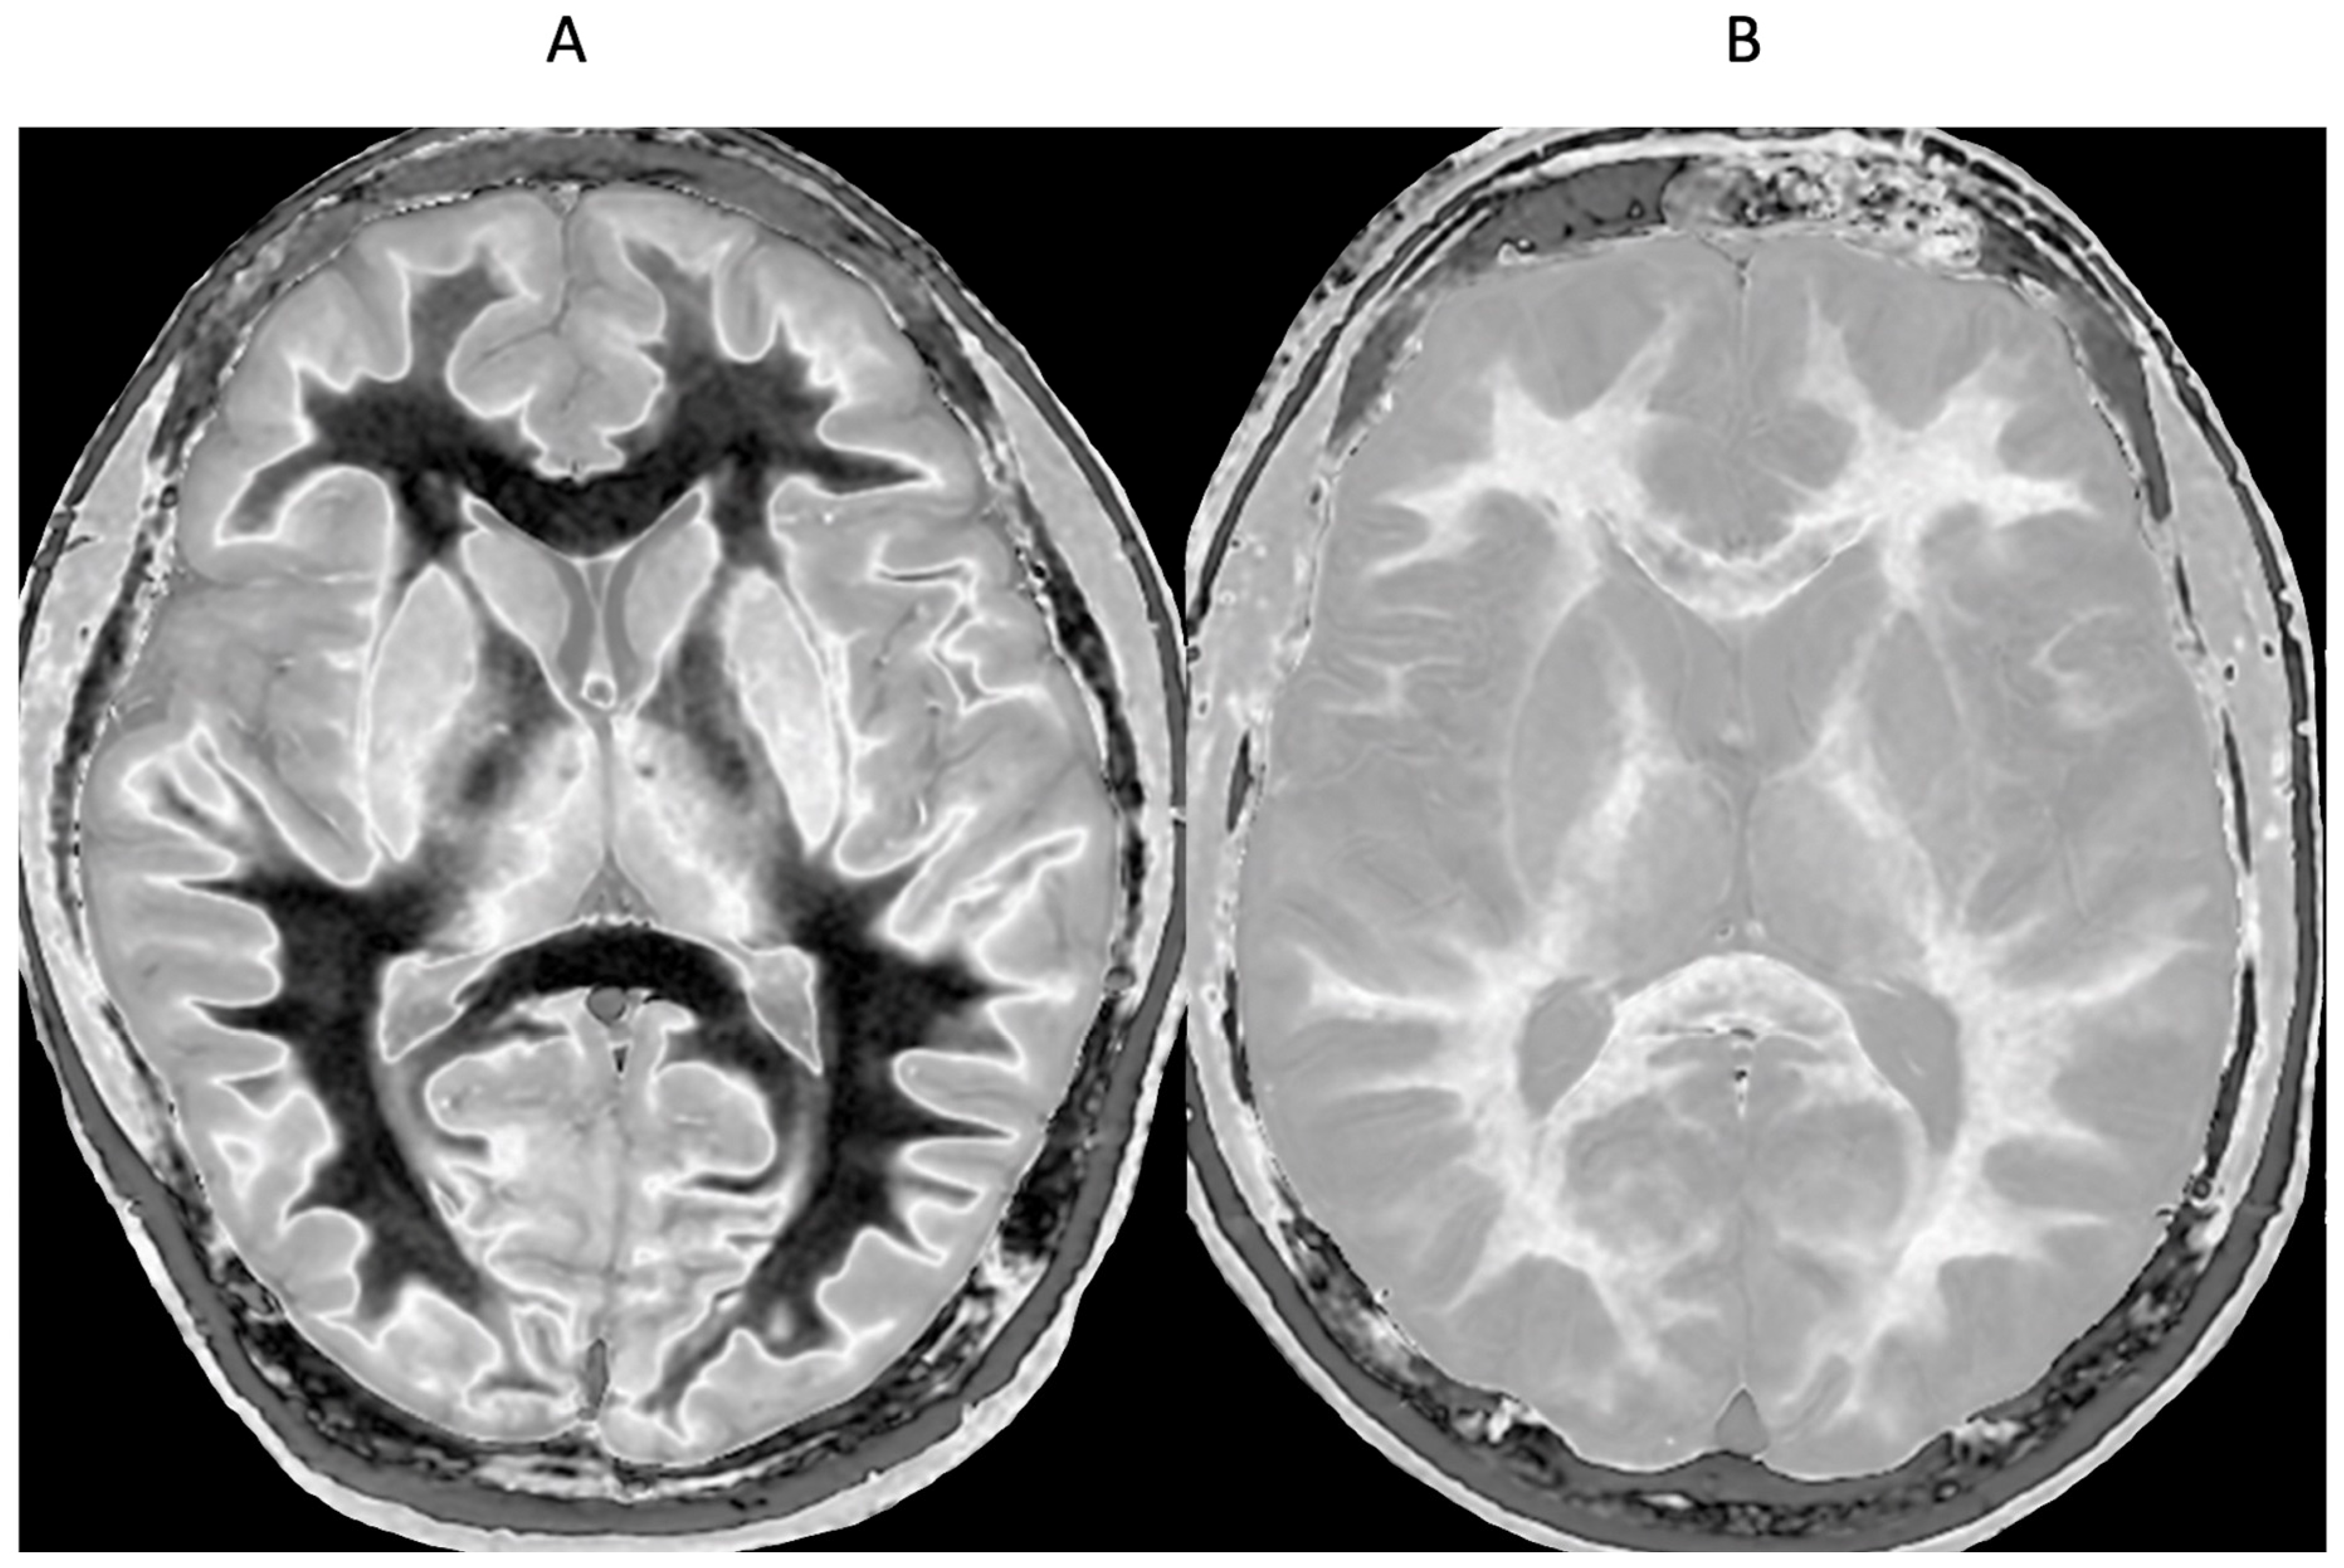

Figure 13.

Normal control (A) and patient with mTBI (B) showing a whiteout sign and grayout signs (narrow mD dSIR images). The normal control shows the heads of the caudate nuclei with higher signal than the adjacent CSF. Contrast is also seen between the cortex and CSF. In (B), the patient shows a whiteout sign. There are grayout signs in the thalami and putamina. In addition, contrast between the heads of the caudate nuclei and CSF is lost and there is little or no contrast between cortex and CSF which are isointense. These are also grayout signs. No abnormality was seen on the T2-FLAIR images in the normal control or patient.